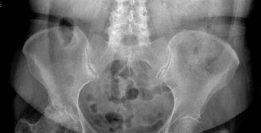

- True Anteroposterior (AP) Pelvis: Standardized view (patient supine, feet internally rotated 15 degrees) to assess joint space, osteophytes, subchondral changes, femoral head migration, bone quality, and pelvic landmarks. Templating for acetabular component size and position is performed.

Clinical & Radiographic Imaging